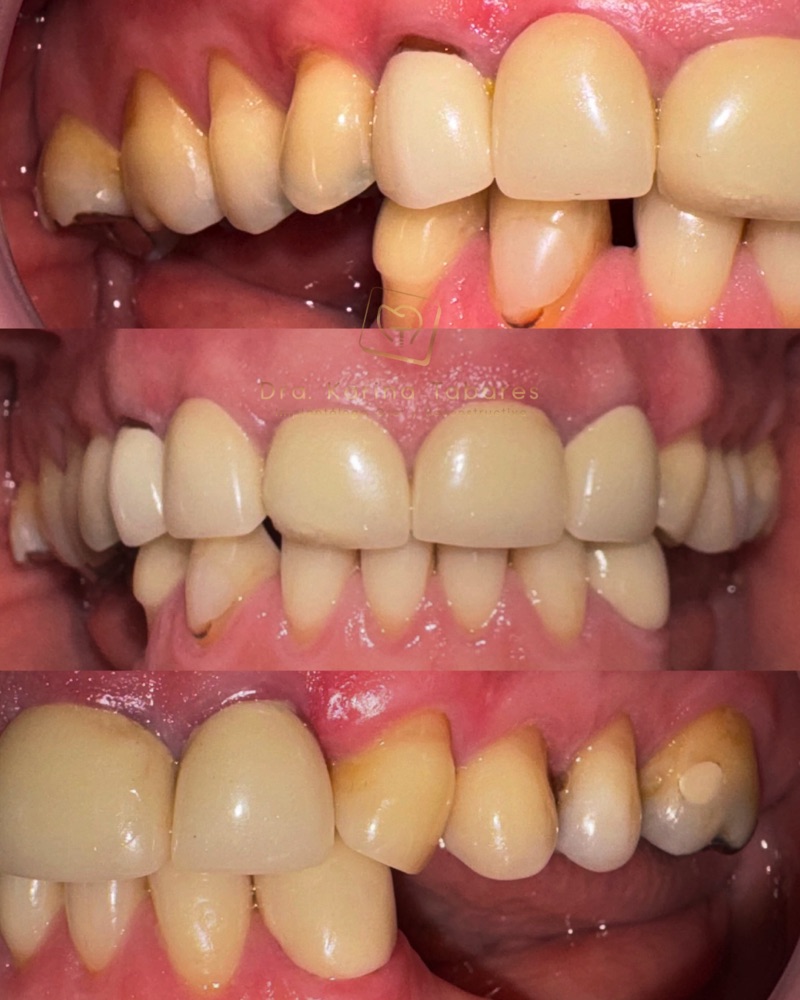

Antes y después

Cientos de pacientes han confiado en el equipo de la Dra. Karina Tabares y hoy comparten experiencias reales que han transformado sus vidas.